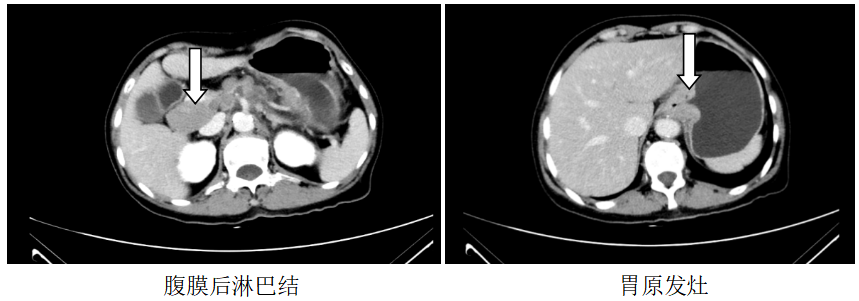

胸部CT:1、左锁骨区、左腋窝多发肿大淋巴结,考虑转移,建议随访,全腹CT:考虑食管胃交界癌累及胃周脂肪并腹腔腹膜后淋巴结多发转移(CT分期约T4aN3)。

诊断:食管胃交界腺癌腹腔、腹膜后、左腋窝、左锁骨区淋巴结转移脑转移(cT4aN3M1,IV期,HER2扩增,MSS,PD-L1-)

图1.2019.7.5影像(基线评估)